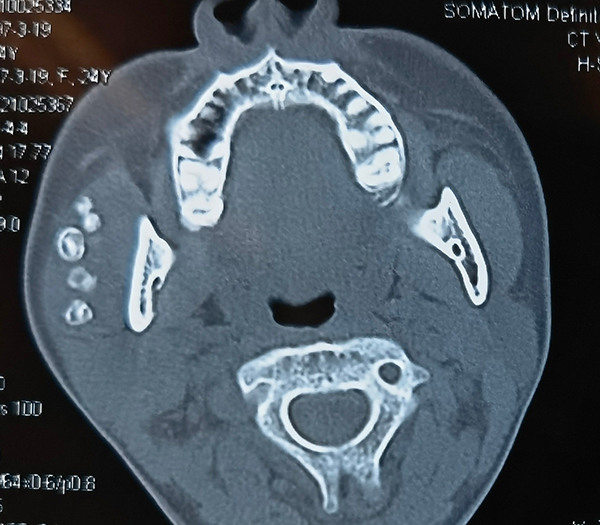

小珍的病史和相关影像学检查提示右腮腺区静脉畸形,颌面部CT提示静脉畸形腔内有多个静脉石。口腔颌面外科何浒杰医师作为小珍的管床医生,非常细心、耐心和小珍讲解病情,减少她对手术的恐惧。